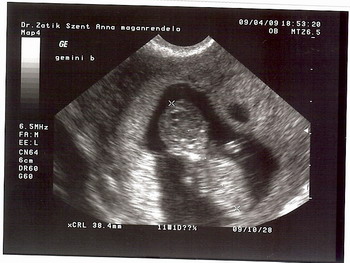

Este UH Dr Zatik Jánosnál (szimpi doki). Mindkét drágánk 38 mm-es, 11 hetes + 1 naposnak felelnek meg, szal szép nagyok. :D És az egyik integetett nekünk meg vizibiciklizett. :) A másik is eleven volt egy pár percig, de aztán megszeppent a "kamerától", és befordult. :lol: